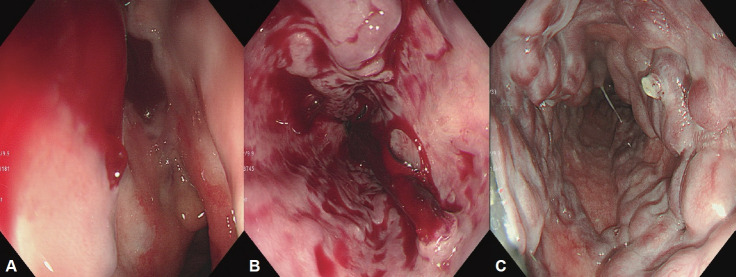

胃食管静脉曲张发生在超过一半的肝硬化患者中,随着肝功能的恶化,发生率增加。尽管随着内窥镜下静脉曲张止血技术的发展以及血管活性药物和预防性抗生素的应用,急性静脉曲张出血的死亡率有所下降,但仍高达20%。因此,对肝硬化患者进行静脉曲张的监测和预防其出血是非常重要的。肝硬化合并门脉高压的患者,应行食管胃十二指肠镜诊断静脉曲张并对其出血风险进行分层。内镜监测间隔根据静脉曲张情况和肝硬化严重程度调整。如果诊断出静脉曲张,则需要一级预防(例如,非选择性β受体阻滞剂或内窥镜预防)来预防静脉曲张出血。急性静脉曲张出血患者应进行适当的治疗,包括及时的内镜止血,并需要二级预防以防止再出血。内镜下静脉曲张结扎是急性食管静脉曲张出血的推荐内镜治疗方法;内镜下静脉曲张梗阻通常推荐用于胃静脉曲张患者。为防止出血,应定期进行内镜监测,直至静脉曲张完全根除,即使静脉曲张消失后也应定期进行内镜随访。在这篇综述中,我们探讨了内镜在胃食管静脉曲张的治疗和管理中的作用。

Gastroesophageal varices occur in more than half of patients with cirrhosis and the incidence increases as liver function worsens. Although the mortality rate for acute variceal bleeding has decreased with the development of variceal endoscopic hemostasis and administration of vasoactive drugs and prophylactic antibiotics, it still reaches 20%. Therefore, surveillance of variceal occurrence and the prevention of their bleeding is very important in patients with cirrhosis. In patients with liver cirrhosis accompanied by portal hypertension, esophagogastroduodenoscopy should be performed to diagnose varices and stratify their bleeding risk. The interval of endoscopic surveillance is adjusted according to variceal condition and cirrhosis severity. If varices are diagnosed, primary prophylaxis (e.g., non-selective beta-blockers or endoscopic prophylaxis) is required to prevent variceal bleeding. Appropriate treatment, including timely endoscopic hemostasis, should be performed in patients with acute variceal bleeding, and secondary prophylaxis is required to prevent rebleeding. Endoscopic variceal ligation is the recommended endoscopic treatment for acute esophageal variceal bleeding; endoscopic variceal obstruction is usually recommended in patients with gastric varices. To prevent bleeding, endoscopic surveillance should be performed at regular intervals until the varices have been eradicated, and endoscopic followup should be performed periodically even after their disappearance. In this review, we investigate the role of endoscopy in the treatment and management of gastroesophageal varices.